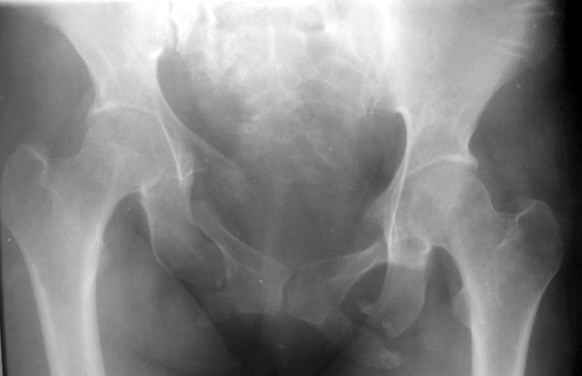

Вопрос Уральскому Пельвиоцентру: через год после травмы, довольно симпатичная женщина, болей нет, только ходит призрамывая на правую ногу и сидит криво, мышечная ассиметрия практически не выражена, хотя слабость справа есть. Легко компенсируется подкладкой стельки 1,5 см с выраженным клиническим эффектом. Посылаю снимки с вопросом - можно ли устранить деформацию в Вашем аппарате, если можно - то поподробнее. Снимки с разницей во времени почти 1 год. Жду ответа как соловей лета. ЛАФ.

У нас в отделении даже куда менее значительные деформации считаются показанием к устранению, тут, конечно, надо постараться улучшить форму.

Для уточнения объема и характера операции надо доснять inlet/outlet проекции и сделать КТ переднего и заднего отделов. Надо уточнить, делать ли остеотомии, или нет сращения и можно закрыто аппаратом разорвать. Ну а схему аппарата ты видел, если ве-таки ее надо, завтра заброшу, если Рунков или Шлыков раньше сами не ответят.

Дело в том, что там непревильно сросшийся перелом боковых масс крестца - Делать ли остетомию - продолженную репозиуию в аппарате, внутреннюю фиксацию переднего и заднего полукольца или вместо всего этого одномоментно удлинить бедро на 1,5 см, в крайнем случае добавить резекцию седалищного бугра слева - прямее будет сидеть.? ЛАФ.

Привет! Случай типичный при такой травме, когда накладывают переднюю раму аппарата, но репозиции не достигают и игнорируют повреждение задних отделов. Интересно узнать всю историю поподробнее, где и как лечилась, сроки, была ли информация у больной, что ей можно было помочь гораздо раньше и с большим эффектом.

На счет жалоб: к году полутора при этом повреждении больные приспосабливаются к новым условиям и активно предъявляют жалобы, как правило, только на боли, с которыми они смирились и хромоту. Перелом боковой массы крестца или срастается или образует достаточно спаек для стабилизации повреждения в отличие от чистых разрывов КП сочленения.

Однако при расспросе картина становится более ясной, т.к. выявляются ограничения в ходьбе, сидении, лежании и способности к труду. Мы пользуемся универсальными шкалами, хорошо бы узнать ее баллы по Majeed. Для уточнения диагноза и степени сращения необходимы дополнительные проекции inlet, outlet и обязательно КТ таза с шагом 0,5мм. Не плохо было бы и общий вид узреть - фас, сзади и стоя на одной ноге.

Объем хирургического пособия зависит от этих данных.

Привожу пример лечения больного с 7 месячной деформацией. Отеотомии - аппарат - внутренняя фиксация.

Рентгенограммы до и через месяц после окончательной стабилизации. Потом поищу более поздние снимки.